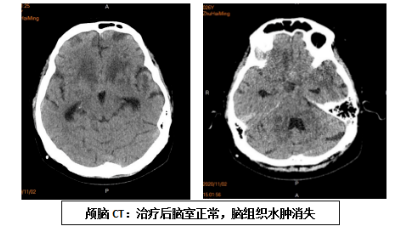

我科与“付继弟颅内感染诊疗团队”进行了密切合作,成立了“中枢神经系统感染诊治中心”,已经成功开展了各种原因引起的颅内、椎管内顽固性严重感染性,和相关神经重症疾病的诊断与治疗,收治的病人来自京外各地医院转来的重症患者。付继弟教授、潘栋超医生亲自参与我科病人的手术及围手术期管理和诊疗工作,经治疗的患者病情均得到有效的转规,好转出院。

我科与首都医科大学附属北京胸科医院建立技术合作,联合“付继弟颅内感染诊疗团队”共同组建了由张立群教授、付继弟教授、张蓬川主任医师、潘栋超和何刚副主任医师组成的“中枢神经系统结核病诊疗团队”,成立了“中枢神经系统结核病诊治中心”,形成了针对“中枢神经系统结核性疾病”的内外科全面系统的诊断及治疗体系,病情均得到有效治疗,病人好转出院。